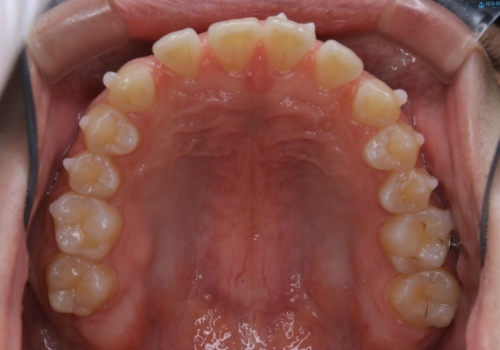

- 上のすきっ歯が気になるとご相談にいらした方です。上下顎ともにスペースがあったため、インビザラインFULLにて見た目と噛み合わせの改善も同時に行いました。

元々は上前歯のみの部分矯正をご希望されていましたが、下の歯もスペースがあり、噛み合わせ的にも上のみの部分治療は難しいことをお話ししました。前歯のみの部分矯正を行った場合、前歯の隙間だけが閉じて奥歯が噛めなくなってしまう場合もあります。インビザラインFULLにて治療することで、噛み合わせと見た目を同時に改善させることができ、大変喜んでいただけました。